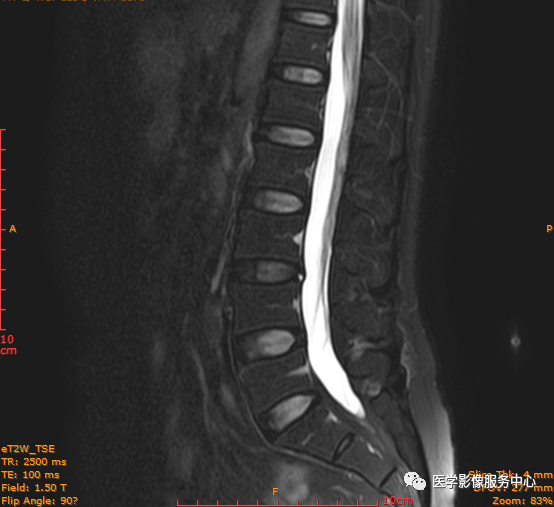

临床诊断 :腰突症?故行腰椎MRI检查,图像如下:

T2矢状位

这个患者腰椎间盘膨出程度不明显,神经根没有明显的受压,椎管未见明显狭窄,那这个患者腰疼的“罪魁祸首”是腰椎间盘膨出嘛?

大家有没有留意到还有哪个地方不正常呢?

L3-4椎间盘后缘可见点状高信号区(红色箭头所指处)

红色箭头所指的异常信号区是是什么呢?平时工作中大家有没有遇到这种情况,你会不会忽略这个异常信号?有没有想过这个椎间盘后缘高信号区是引起患者腰疼的重要因素呢?下面为大家重点介绍。

影像表现主要在T2矢状位及T2横断位可见椎间盘前缘或后缘可见高信号区;

L3-4椎间盘后缘HIZ